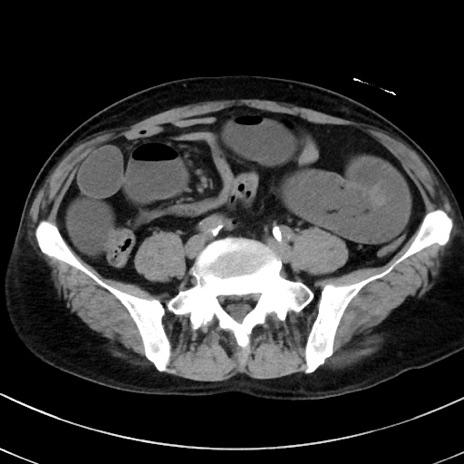

冠状断像

【症例】70歳代 男性

【主訴】腹痛・嘔吐

【現病歴】昨晩より、嘔吐・腹痛あり。今朝になっても嘔吐あり。来院。

【既往歴】心臓バイパス手術、開腹胆摘、腸閉塞

【身体所見】BP 107/71mmHg、HR 116/min、腹部:平坦、軟、下腹部に軽度圧痛あり。反跳痛なし。

【データ】WBC 15100、CRP 0.32